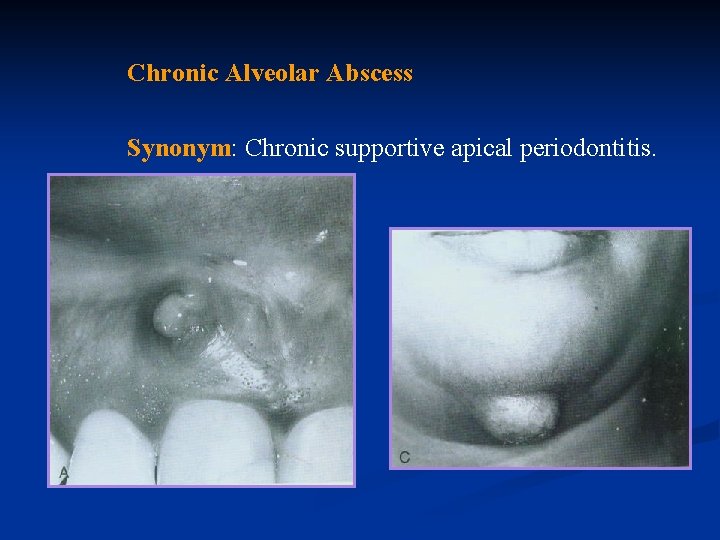

Chronic Alveolar Abscess Synonym: Chronic supportive apical periodontitis.

Definition: A chronic alveolar abscess is a long-standing, low –grade infection periradicular alveolar bone. The source of the infection is in the root canal.

Cause: Chronic alveolar abscess is a natural sequela of a death of the pulp with extension of the infective process periapically, or it may result from a pre-existing acute abscess.

Symptoms: A tooth with chronic alveolar abscess is generally asymptomatic; at times, such an abscess is detected only during routine radiographic examination or because of the presence of a sinus tract.

Diagnosis: A chronic abscess may be painless or only mildly painful. At times, the first sign of osseous breakdown is radiographic evidence seen during routine examination or discoloration of the crown of the tooth.

When asked, the patient may remember a sudden, sharp pain that subsided and has not recurred, or he may relate a history of traumatic injury. The tooth does not react to the electric pulp test or to thermal tests.

As a result, a proper and accurate diagnosis can be made only when tissue specimen has been examined microscopically Differential Diagnosis: A chronic abscess should be differentiated from cementoma or ossifying fibroma, which is associated treatment. with a vital tooth and requires no endodontic

Treatment: Treatment consists of elimination of infection in the root canal.